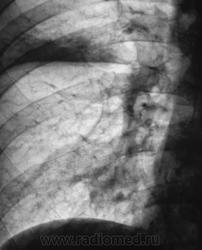

Перисциссурит. Эта форма крупозной пневмонии скиалогически отображается в виде синдрома «Затемнения без анатомических границ», при которой участки воспалительной инфильтрации локализуются по ходу междолевых щелей (плевры), по периферии долей и отделены от грудной стенки массивом «не пораженной легочной ткани».

Для перисциссурита характерно:

- чёткий контур по ходу междолевой плевры, нечеткость контуров с интактной легочной тканью;

- визуализация просветов сегментарных и субсегментарных бронхов на фоне инфильтрированной легочной ткани;

- стандартная конфигурация междолевых щелей, что свидетельствует об отсутствии объёмного уменьшения;

- некоторая гомогенизация и расширение тени корня на уровне патологического процесса

на представленное клиническое наблюдение, возможно, подумал про себя, «да ведь это самый обыкновенный краевой инфильтрат, который я много раз описывал». Однако врача берет сомнение, а вдруг автор (В.Л. Катенёв) расставил силки. Думая о «силках», врач не хочет оказаться в неприятном, неловком, невыгодном для себя положении. Хотя этого врача почти никто не знает в этом мире. В маске он совсем неузнаваем. Проклятые комплексы не дают человеку полной свободы во всем. Поэтому ответов всего три на 100-120 участников и посетителей сайта. Мое мнение - перисциссурит. На вопрос автора «что в данном случае свидетельствует об ателектазе?» хочу ответить. Любая пневмония сопровождается апневматозом различной степени, особенно перисциссурит (мои личные выводы). О нарушении бронхиальной проходимости здесь свидетельствуют: 1) смещение горизонтальной междолевой щели вверх; 2) увеличение прозрачности легкого в проекции S3. (см. рисунок). Если я ошибся, не беда. Доктора, знающие больше меня, поправят. На сайте все учатся. Жду мнений других врачей.

А, динамика известна. Через 14 дней после проведения противовоспалительного лечения (неспецифического), рентгенологически - норма.